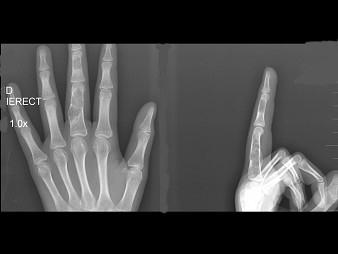

问题 男,15岁,左侧中指局部肿胀,无压痛,关节活动无明显异常,结合图像,最可能诊断是?(?)

选项 A.骨质疏松 B.内生软骨瘤 C.骨巨细胞瘤 D.骨囊肿 E.动脉瘤样骨囊肿

答案 B